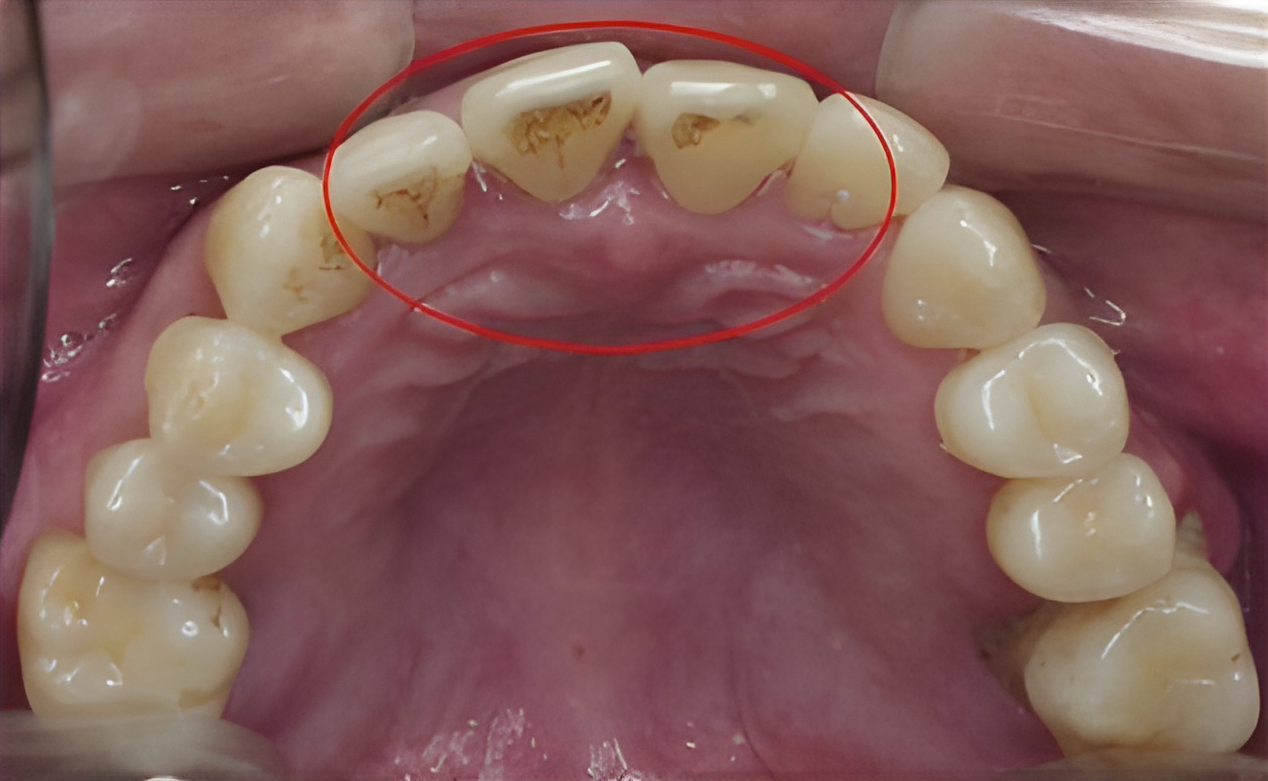

Before

When it comes to dental treatment, nothing is more important than preventive care. A regular dental check-up and teeth cleaning prevents the development of serious dental problems that can require costly treatments. During a teeth cleaning, our licensed dental hygienist removes soft and hard deposits from your teeth and polishes the surfaces of your teeth.

It is recommended that you visit a dentist regularly once every six months. We send out a reminder for your next check-up appointment so you can maintain proper oral hygiene.